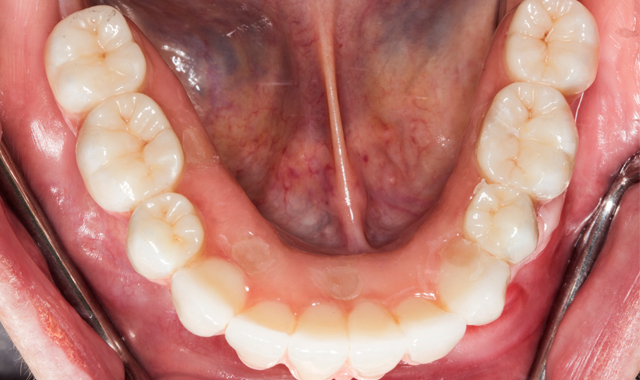

A 70-year-old patient presented with fractured teeth and multiple failing restorations (Fig. 1-2). It was determined that the mandibular teeth were not restorable. The treatment plan was for a mandibular fixed detachable prosthesis with five implants. Due to patient’s finances, the maxillary arch will be restored after the mandibular arch is finished.

A full thickness flap was performed, as well as extraction of remaining mandibular teeth with alveoloplasty to create restorative space and achieve an even ridge. A clear duplicate surgical guide was used for implant position and distribution. Five BioHorizons Tapered Internal implants were placed using a second stage approach (Fig. 3).

After an uneventful healing period, uncovery of the implants was performed and multi-unit abutments were placed and torqued to 30NCM (Fig. 4).